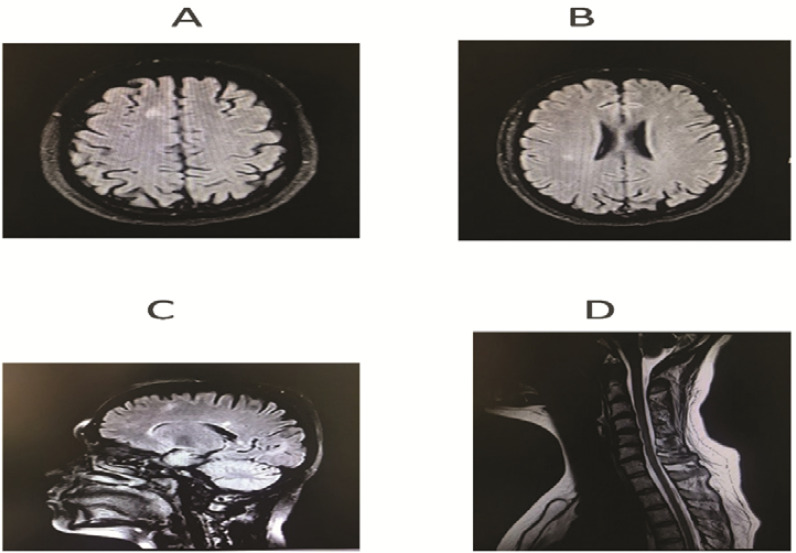

Initial clinical presentation of multiple sclerosis with concurrent COVID-19 infection: Case report and literature review.